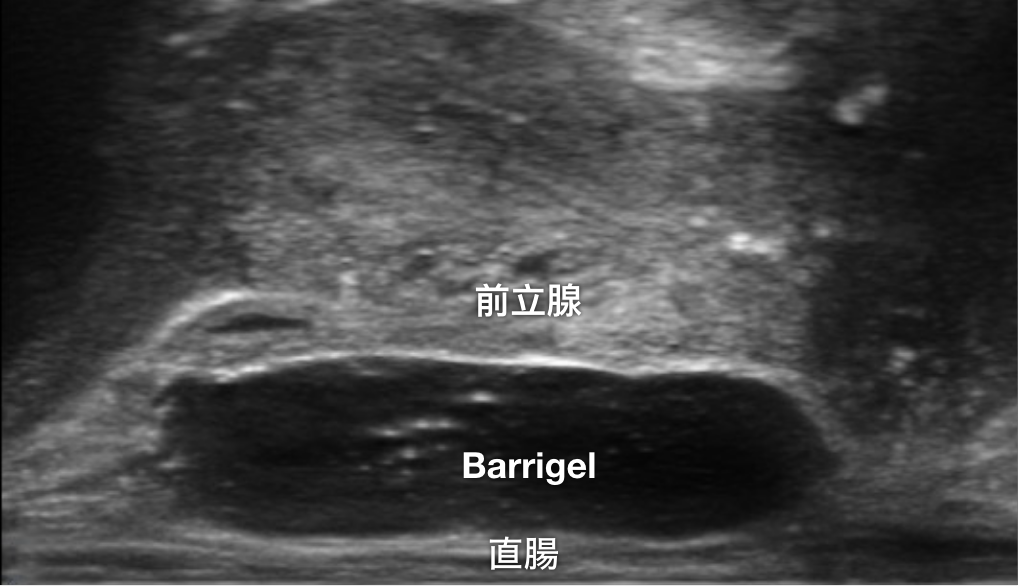

TRUS 画像

TRUS画像提供:Neil F. Mariados, MD

Radiation Oncologist; New York, United States